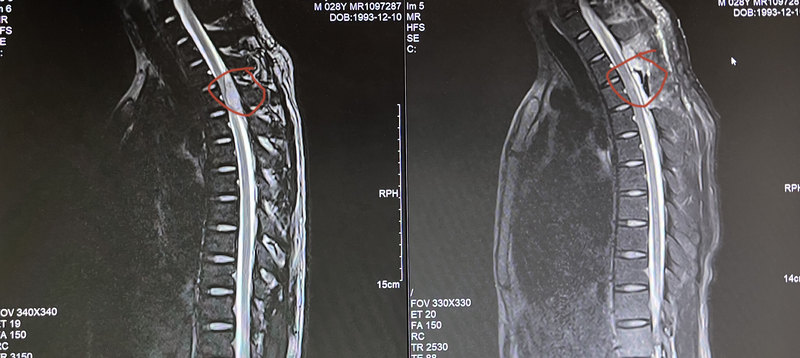

脊髓硬脊膜外出血有多可怕?

前几天值班碰到一个脊髓硬脊膜外出血的病人,病程非常凶险,给大家介绍一下。这是一个28岁的青年男性,因出现不明原因的突发颈胸背部疼痛并逐渐加重数小时而到我院急诊科就诊,就诊过程中出现小便无法自行解出,B超提示膀胱残余尿量增多。同时患者双下肢肌力进行性下降,凌晨两点钟左右,下肢肌力仅有两级(即无法自行抬离床面)。首诊神经内科医生马上给予颈胸部CT扫描,仅仅发现胸3水平的椎管内模糊的高密度信号影,怀疑可能有肿瘤合并出血或者血肿可能。值班的神经内科医生马上电话联系我们神经外科紧急会。诊。我去急诊室查看了一下这个病人,感觉平面大概胸4/5左右,能够和胸3的病变对得上,但是仅靠一张模糊的CT影像无法做出准确的判断,更不能单纯根据这张CT片就冒然进行动刀,万一开刀开进去没有出血怎么办。我反复仔细看这张CT片,总感觉不能排除硬膜外出血可能,但当时是后半夜凌晨,磁共振没有急诊值班人员(平时磁共振急诊不开放,仅开放CT急诊),而这个病人不做磁共振无法明确病因。遂紧急联系医院当晚行政总值班,通过总值班联系放射科主任,安排了一位可以进行磁共振检查的医师凌晨从家中赶到医院帮患者完成紧急胸椎磁共振扫描,果然发现患者胸3椎体位置硬脊膜外出血。这就是我们最担心的检查结果,也是我们后半夜为病人行急诊磁共振检查的目的,就是怕这种进展迅速的脊髓硬脊膜外出血。完成检查后马上送手术室紧急行椎板减压血肿清除手术,术后患者很快下肢肌力明显改善。三天后患者双下肢肌力逐渐恢复接近正常水平。自发的脊髓硬脊膜外血肿非常少见,但是致残率非常高。通常以颈肩背部急性疼痛为首发症状,伴进行性脊髓受压表现,往往引起严重的神经功能缺失症状,如截瘫,大小便失禁,更严重者(更高位者)呼吸功能会受损,致死致残率非常高。早期诊断,正确处理这种疾病,对挽救患者脊髓功能具有非常重要的意义。不是每个此类病人都能有好的结局,笔者最近数年中,急诊值班中曾经碰到过几例这样的病人,包括一位很年轻大概30岁出头的女性患者,因病情进展迅速,到达我院急诊室的时候双下肢肌力已经是0级状态(双下肢不能进行任何自主活动,甚至没有肌肉收缩),虽然马上进行了急诊手术清除硬脊膜外血肿并进行椎板减压,但最后经过很长时间的康复,仍然无法恢复下肢肌力和大小便功能,最后的结局是终身瘫痪在床。病程进展快速导致脊髓功能逐步恶化的此类病人必须明确诊断后进行急诊手术处理!这位年轻小伙子比较幸运,我们及时做出了正确的判断,并进行了急诊手术减压,患者很快得到了恢复。